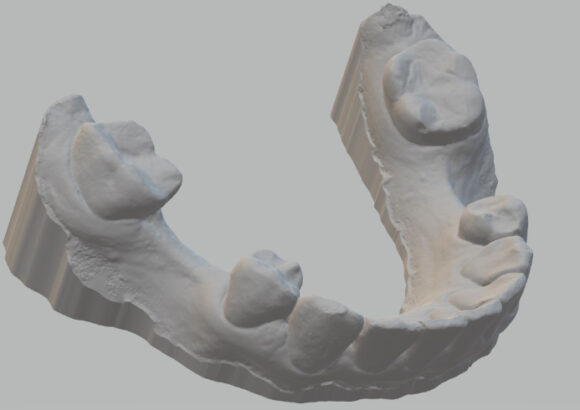

El escaneo dental es un dispositivo digital utilizado para capturar impresiones tridimensionales de la boca del paciente.

Este tipo de escaneo permite recrear la dentadura con una precisión que supera con mucho las muestras tomadas con materiales de impresión tradicionales.

• Réplica exacta de las estructuras dentales y tejidos adyacentes del paciente.

• La ventaja es que su consulta se actualiza dejando atrás modelos de yeso que se rompen o maltratan y que además debe de almacenar. Le damos la alternativa de almacenarlos digitalmente teniéndolos virtualmente en su computadora y si requiere imprimirlos podemos realizarlo en el momento que necesite.

• Los escaneos son considerados tan precisos si no más exacto que los moldes de yeso. El proceso de escaneo es más cómodo para pacientes especialmente con reflejo nauseoso.

• Mayor precisión comparado con modelos convencionales de alginato, sin necesidad de repetir la toma de impresión.